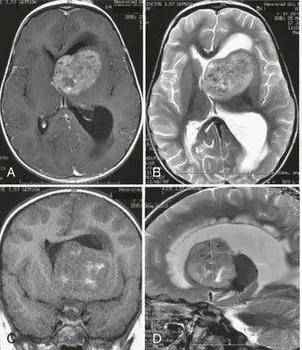

巨大的侧脑室占位

然而,意外情况突然发生。就在家人四处咨询期间,文文的病情出现了急剧变化。她突发意识模糊,继而陷入昏迷状态。接到家人电话通知时,文文母亲的心情瞬间沉入谷底。她迅速赶往急诊室,医生告知文文出现了梗阻性脑积水的症状,必须立即接受手术干预。时间紧迫,不容犹豫,文文母亲只能目送女儿被推进手术室。手术很快完成,医生首先为文文放置了外部脑室引流管以缓解梗阻性脑积水,但导致积水的根本病因——肿瘤,并未被清除,因此后续手术依然势在必行。

最终,这场由巴教授主刀的手术取得了成功。在术中磁共振与术中神经导航技术的辅助下,肿瘤被精准地完全切除。术后病理报告证实为室管膜瘤,分级为3级。术后,文文未出现任何新的神经功能损伤。鉴于肿瘤的恶性性质,她后续仍需接受放疗与化疗,以控制肿瘤复发的风险。